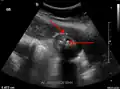

Right upper quadrant abdominal ultrasound is most commonly used to diagnose cholecystitis.[1][26][27] Ultrasound findings suggestive of acute cholecystitis include gallstones, pericholecystic fluid (fluid surrounding the gallbladder), gallbladder wall thickening (wall thickness over 3 mm),[28] dilation of the bile duct, and sonographic Murphy's sign.[13] Given its higher sensitivity, hepatic iminodiacetic acid (HIDA) scan can be used if ultrasound is not diagnostic.[13][14] CT scan may also be used if complications such as perforation or gangrene are suspected.[14]

Abdominal ultrasonography showing gallstones, wall thickening and fluid around the gall bladder -

Acute cholecystitis as seen on ultrasound. The closed arrow points to gallbladder wall thickening. Open arrow points to stones in the GB -

Acute cholecystitis with gallbladder wall thickening, a large gallstone, and a large gallbladder -